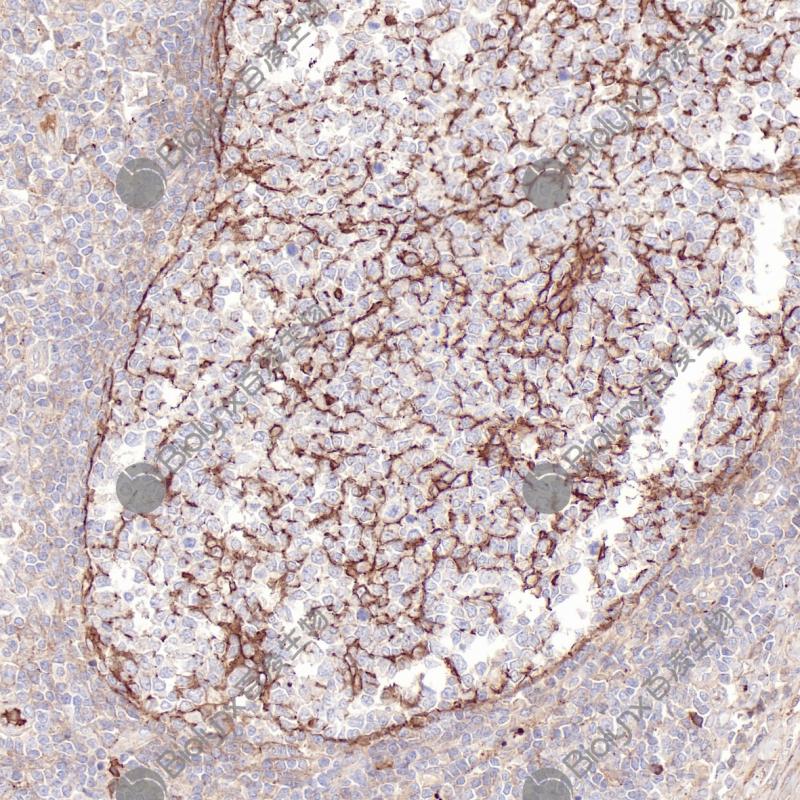

Tyrosine Hydroxylase 重组兔单克隆抗体

酪氨酸羟化酶(Tyrosine Hydroxylase,TH)作为多巴胺合成的限速酶,催化L-酪氨酸转化为L-DOPA,是多巴胺能神经元的经典标志物。TH主要在中枢和外周神经组织、肾上腺髓质和副神经节瘤中表达。在临床病理诊断中,TH主要用于副神经节瘤的辅助诊断,具有较高的特异性和敏感性。

阳性对照

副神经节瘤

亚细胞定位

细胞质